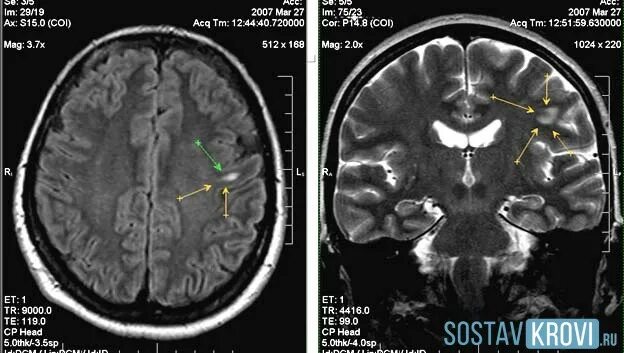

Очаги в белом веществе сосудистого характера. Мрт множественные очаговые изменения вещества головного мозга. Очаги в белом веществе сосудистого характера. Очаговые изменения вещества мозга дистрофического. Единичные очаги сосудистого генеза.

Очаги в белом веществе сосудистого характера. Множественные очаги в белом веществе. Глиозные очаги головного мозга мрт. Очаги в белом веществе сосудистого характера. Очаговые изменения головного мозга дисциркуляторного характера мрт.

Очаги в белом веществе сосудистого характера. Множественные мелкие очаги в белом веществе головного мозга. Очаги дисциркуляторного характера мрт. Дисциркуляторная энцефалопатия головного мозга на кт. Очаговые сосудистые изменения головного мозга.

Мр картина очаговых изменений вещества мозга. Сосудистые изменения белого вещества головного мозга. Очаги микроангиопатии в белом веществе головного мозга. Очаги в белом веществе сосудистого характера. Очаги в белом веществе сосудистого характера.

Мрт головного мозга заключение очаговые изменения. Очаговые изменения серого вещества головного мозга мрт. Субкортикальные очаги в белом веществе головного мозга мрт. Лакунарный глиоз. Перивентрикулярные очаги в белом веществе.